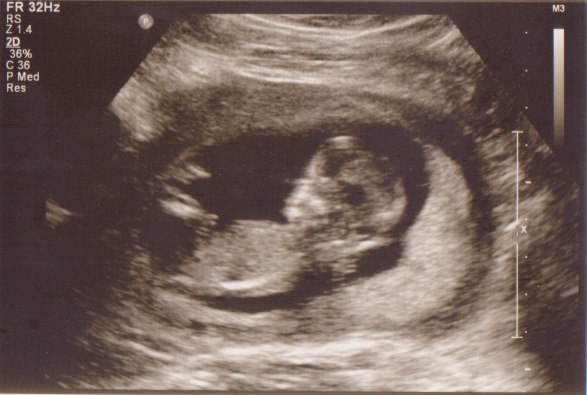

Vi fik med det samme øje på den lille guldklump som lå og hyggede sig gevaldigt inde i sin babyhule - h*n kunne slet ikke ligge stille, så det tog lidt tid inden hun fik målt nakkefolden, men i mellemtiden viste hun os hjernehalvdelene, mavesækken, næsebenet, alle 5 fingre på den ene hånd - kan næsten ikke huske alt det hun viste os - det var bare så fantastisk